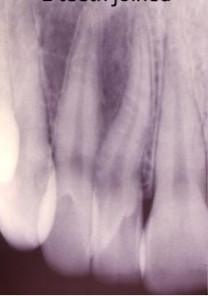

dens invaginitis/dens in dente

what is the diagnosis?

type I

dens in dente in which invagination is CONFINED TO CROWN

type II

dens in dente in which invagination extends BLEOW CEJ

type III

dens in dente with invagination extending through the ROOT